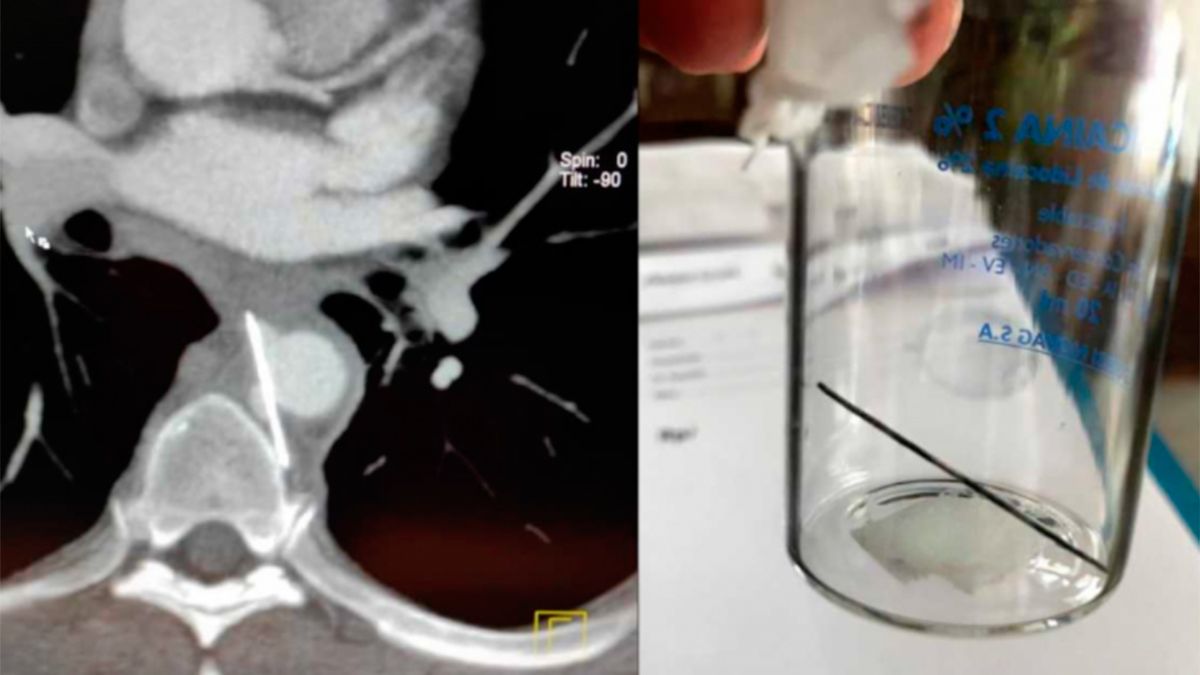

"La aguja era de tres centímetros y medio perforó el esófago y quedó alojado entre la arteria aorta y la vértebra. La misma fue detectada por una tomografía computada. Y por suerte a la semana el esófago ya estaba cerrado y no había pérdida y podía ingerir comida", contó Desiderio.

El médico explicó que la operación que llevaron a cabo este miércoles por la mañana consistió en que le pusieron un stent ante la probabilidad de que esa aguja le perforara la aorta.